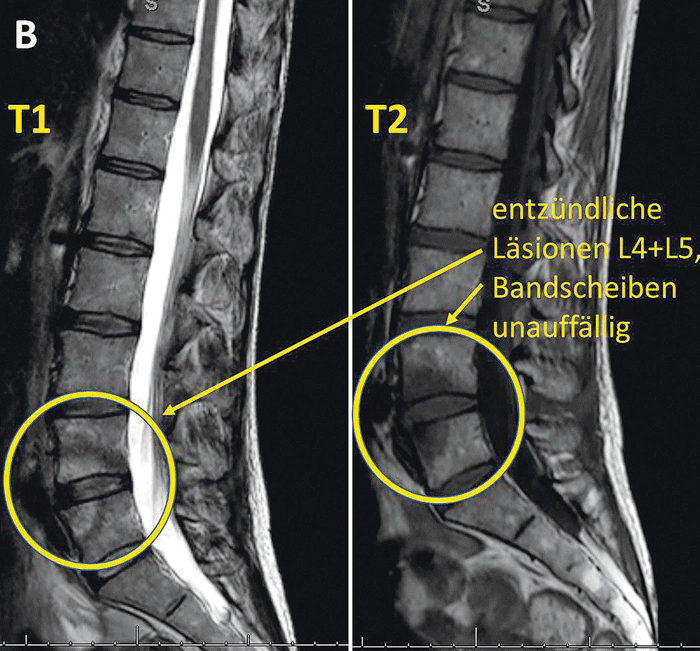

Im MRT zeigte sich eine Ödembildung im Bereich L4/5, woraufhin zwei Ganzkörper-Skelettszintigraphien im Abstand von neun Monaten durchgeführt wurden. Sie ergaben jedoch keinen Hinweis auf einen neoplastischen Prozess. Als Hautveränderungen an den Füßen auftraten, suchte die Patientin einen Hautarzt auf, der eine Psoriasis pus­tulosa plantaris diagnostizierte. Zusätzlich füllte die Patientin dort den GEPARD-Fragebogen aus, der den Verdacht erhärtete. Prof. Dr. Härle bestätigte schließlich die Diagnose einer Psoriasis-Arthritis mit Spondylitis L4/5.